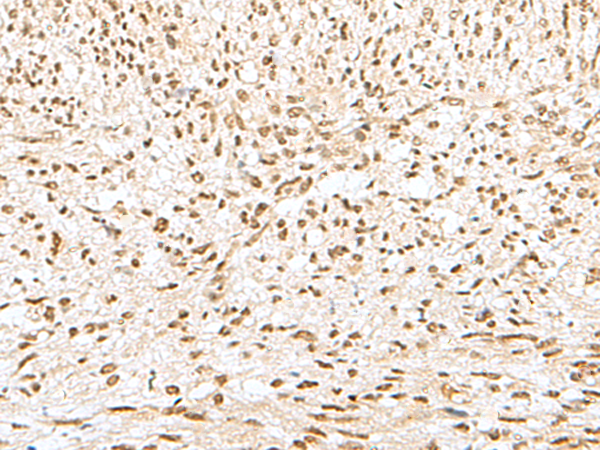

IHC positive control:

Human liver cancer and Human tonsil

IHC Recommend dilution:

30-150